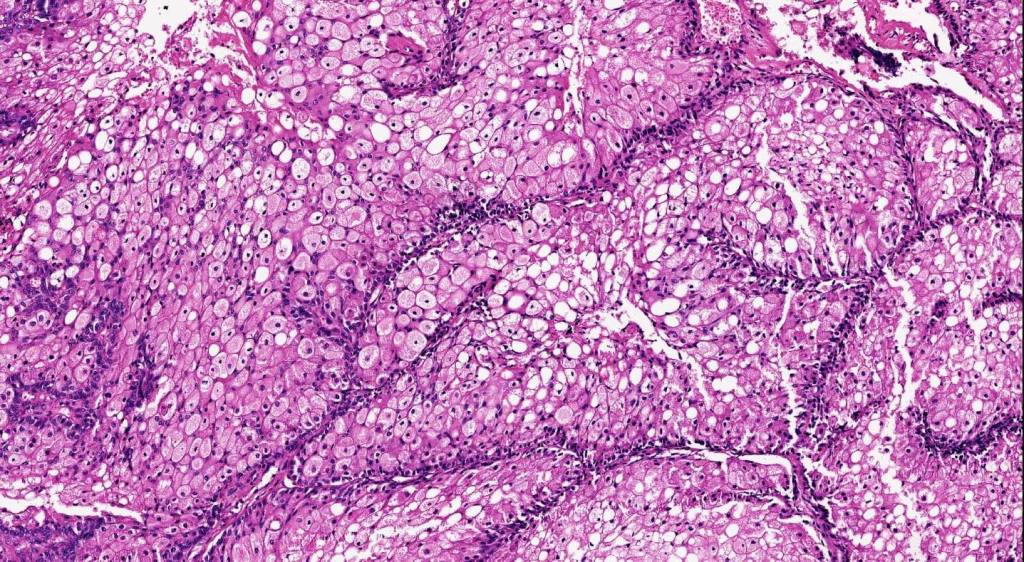

Histological features

•Variable origin from epidermis

•Typically multilobulated, occasioanlly cystic

•Collagenous pseudocapsule

•At the periphery, single or multiple germinative cell layers maturing into typical sebaceous cells (>50%)

•Variable peripheral palisading

•+/- basal mitoses (particularly in the so-called giant variant which should not be misdiagnosed as sebaceous carcinoma)